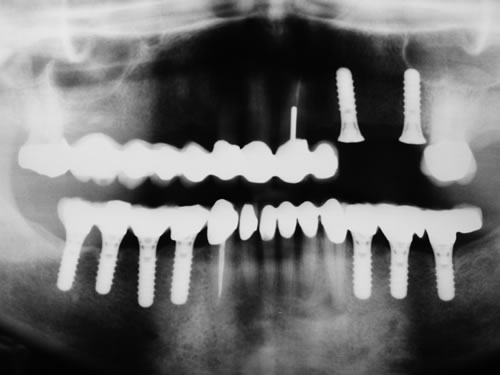

Abb. 3.13: Zahnloser Unterkiefer mit 8 Implantaten festsitzend versorgt.

Abb. 3.14: Ansicht der einzementierten Brücke.